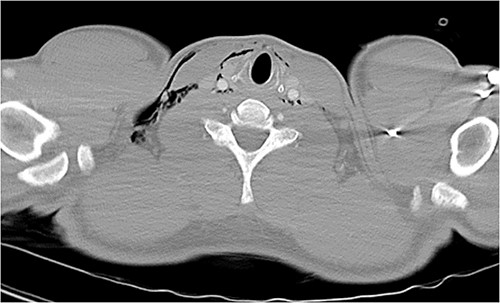

Following extubation, bilateral chest wall subcutaneous emphysema was noted extending to the neck. He also complained of central chest discomfort, without respiratory distress, oxygen desaturation or airway obstruction. Chest X-ray (CXR) revealed pneumomediastinum and surgical emphysema in the lateral chest walls bilaterally. Computed tomography (CT) of the chest, abdomen and pelvis demonstrated large volume subcutaneous emphysema bilaterally in the scrotum, abdominal and chest walls extending to the neck (see Figs 2–5). Gas was noted between the abdominal muscle layers, extraperitoneal and retroperitoneal spaces without pneumoperitoneum (see Figs 5–6). Moderate pneumomediastinum was prominent within the superior and antero-inferior mediastinum without evidence of tracheal or oesophageal injury and an associated small left pneumothorax was noted (see Figs 1–3).

CT chest axial, small left pneumothorax and chest wall subcutaneous emphysema.

CT chest and neck axial, subcutaneous emphysema extending to neck.